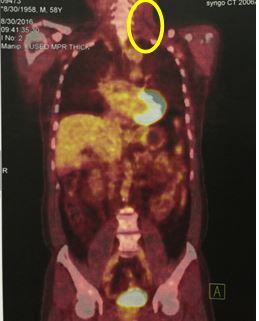

v Chụp PET/CT sau điều trị: khối hạch cổ trái tan biến hoàn toàn, không thấy tăng hấp thu FDG tại cơ quan bộ phận khác của cơ thể.

Hình 2: hình ảnh chụp PET/CT sau điều trị cho thấy khối hạch cổ trái tan biến hoàn toàn, không thấy tăng hấp thu FDG tại cơ quan bộ phận khác của cơ thể.